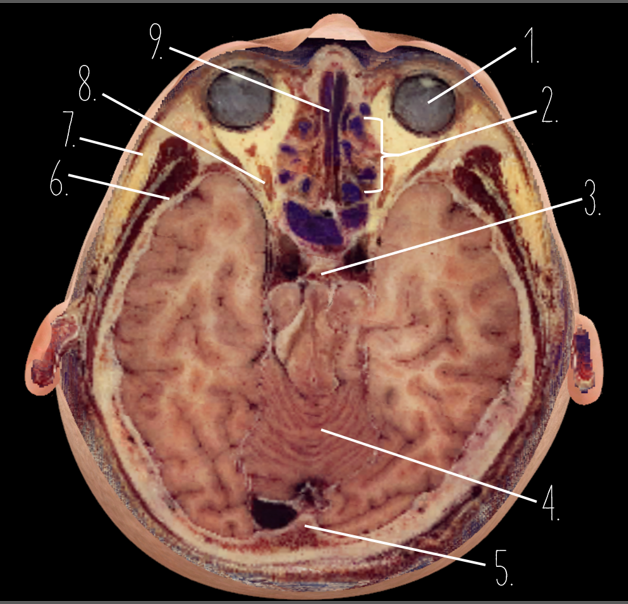

1?

Globe of Eye

2?

Ethmoid Sinus

3?

Pituitary Gland

4?

Cerebellum

5?

Internal Occipital Protuberance

6?

Wing of Sphenoid

7?

Zygomatic Arch

8?

Optic Nerve

9?

Vomer